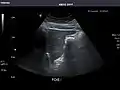

- Left kidney

Kidneys: Right and left kidneys measure 11.5 cm and 12 cm in length respectively. No hydronephrosis. Small left lower pole kidney cyst.